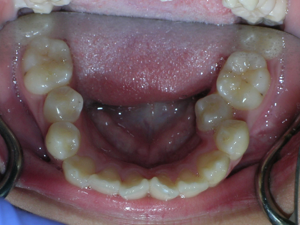

So here’s a case of an open bite, with a protrusion. There was a fair degree of crowding as well.

We decided to do porcelain brackets and have select teeth removed. Take a look.